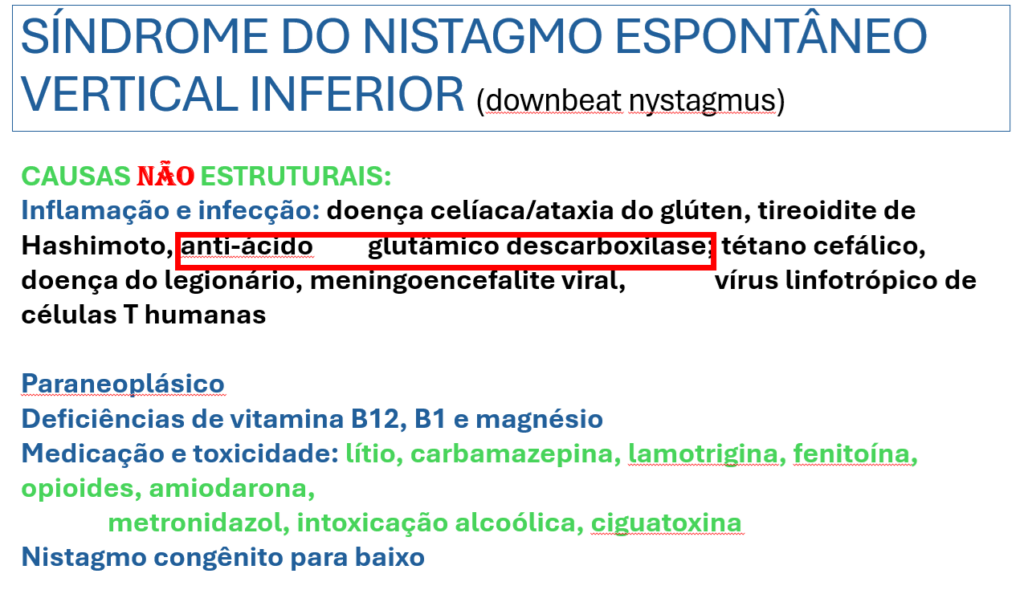

O resultado foi positivo na dosagem do Anti-GAD.

Anticorpo anti-GAD associados ao NVI está como causa inflamatoria ou autoimune.

Autoanticorpos contra o GAD (GAD = ENZIMA chamada acido glutâmico descarboxilase.

A enzima ácido glutâmico dexcarboxilase (GAD) é a enzima que catalisa a conversão do ácido glutâmico em ácido gama-amino butírico (GABA), um neurotransmissor inibitório. Anticorpos contra GAD (anti-GAD-Ab) estão associados a uma variedade de condições neurológicas autoimunes, como síndrome da pessoa rígida, ataxia cerebelar, epilepsia e encefalite límbica. O espectro clínico da ataxia associada com anti-GAD-Ab abrange a síndrome de ataxia cerebelar progressiva lentamente, evoluindo em meses ou anos, associada à atrofia cerebelar na ressonância magnética cerebral. Há poucos relatos de pacientes com ataxia associada com anti-GAD-Ab apresentando movimentos oculares anormais, como NEVI.

Os anticorpos contra o GAD acabam interferindo na síntese do GABA nas células de Purkinje gabaérgicas do floculo-cerebelar.

As células de Purkinje do floculo-cerebelar são especialmente sensitivas para movimentos visuais para baixo. Essa células enviam projeções inibitórias aos canais semicirculares anteriores mas não para os posteriores. Com isso, o dano flocular gera um “drive” dos olhos para cima (componente lenta do nistagmo). A formação reticular gera a componente rápida para baixo = NEVI.

Nossa paciente foi para investigação no serviço de Neurologia e posteriormente para o serviço de neuroimunologia.

Coloco abaixo do lado esquerdo as opções de tratamento utilizadas no NEVI e do lado direito o tratamento indicado para esse caso.